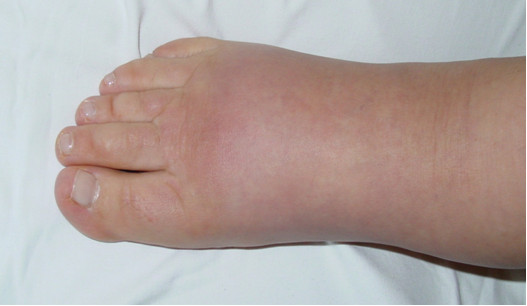

U 24-letniej kobiety w kilka miesięcy po porodzie wystąpił obrzęk kończyny dolnej lewej. Obrzęk pojawił się na stopie obejmując w kolejnych miesiącach dalszą część podudzia. Początkowo obrzęk występował tylko w godzinach wieczornych, później uległ utrwaleniu. W badaniu stopy stwierdzono objaw widoczny na załączonym zdjęciu. Całość obrazu klinicznego może świadczyć o wystąpieniu: